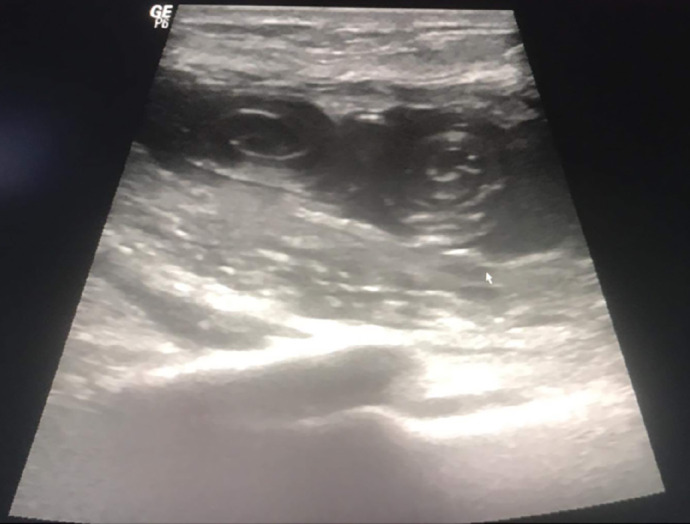

虽然罕见,但乳腺包虫病代表乳腺假瘤。我们提出的情况下,49岁的妇女没有明显的病史,谁被诊断为孤立的包虫囊肿的乳房组织病理检查证实。该患者因乳房不对称和左乳感觉沉重而就诊,无全身包虫病的临床体征。超声乳房x光检查提示诊断,术后组织病理检查证实。虽然很少报道,原发性乳腺包虫病可引起类似肿瘤的症状。手术切除被证明是治疗这种类型乳腺囊肿的有效方法。

Although rare, a hydatid cyst of the breast represents a mammary pseudotumor. We present the case of a 49-year-old woman with no significant medical history, who was diagnosed with an isolated hydatid cyst of the breast confirmed by histopathological examination. This patient consulted for breast asymmetry and a feeling of heaviness in the left breast, with no clinical signs of systemic hydatidosis. The diagnosis was suggested by echo-mammography and confirmed postoperatively by histopathological examination. Although rarely reported, primary hydatid cyst of the breast can cause symptoms that mimic neoplasia. Surgical excision alone proved effective in treating this type of breast cyst.